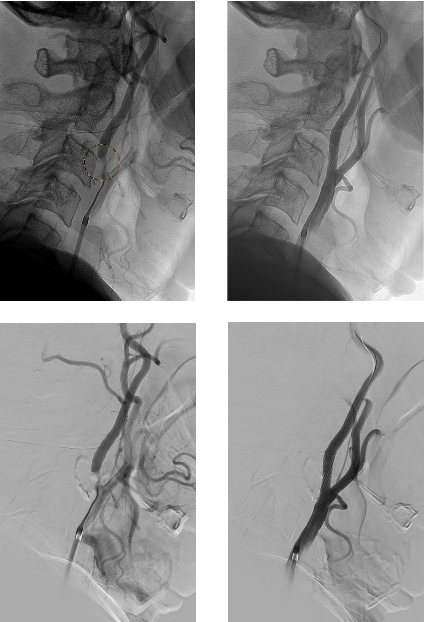

Die mit orangem Kreis markierte hochgradige Engstelle des Abganges der hirnversorgenden Halsarterie kann mittels Stent und Ballon-Aufdehnung (PTA) schonend beseitigt werden.

Bilder links vor dem Eingriff.                 Bilder rechts nach dem Eingriff.